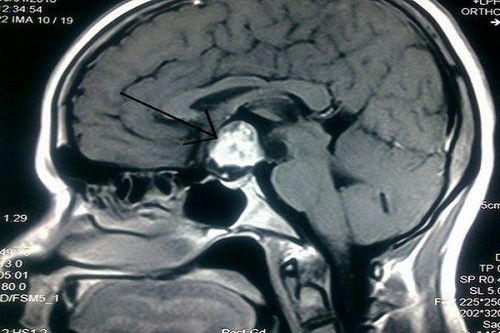

Trong hệ nội tiết phức tạp của cơ thể, tuyến yên là cơ quan đóng vai trò quan trọng không thể thay thế. Kích thước của tuyến yên khá nhỏ, đường kính khoảng 1cm, và khối lượng trung bình khoảng 1 gram. Vị trí của tuyến yên nằm ở nền sọ, trong hố yên. Nhiệm vụ chính của tuyến yên là giám sát và điều chỉnh hoạt động của các tuyến nội tiết còn lại trong cơ thể cùng với hệ thần kinh để đảm bảo sự nhịp nhàng trong việc chế tiết các hóc môn và điều hòa môi trường nội môi của cơ thể. Vì thế, tuyến yên còn được gọi là nút chủ nhịp cho hệ thống các tuyến nội tiết ở người.

- Phát hiện được các tổn thương có kích thước nhỏ tại tuyến yên nhờ khả năng tạo ảnh chi tiết, có độ tương phản cao. Hình ảnh tuyến yên thu được khi chụp cộng hưởng từ tuyến yên rõ nét hơn rất nhiều lần khi chụp cộng hưởng từ sọ não.